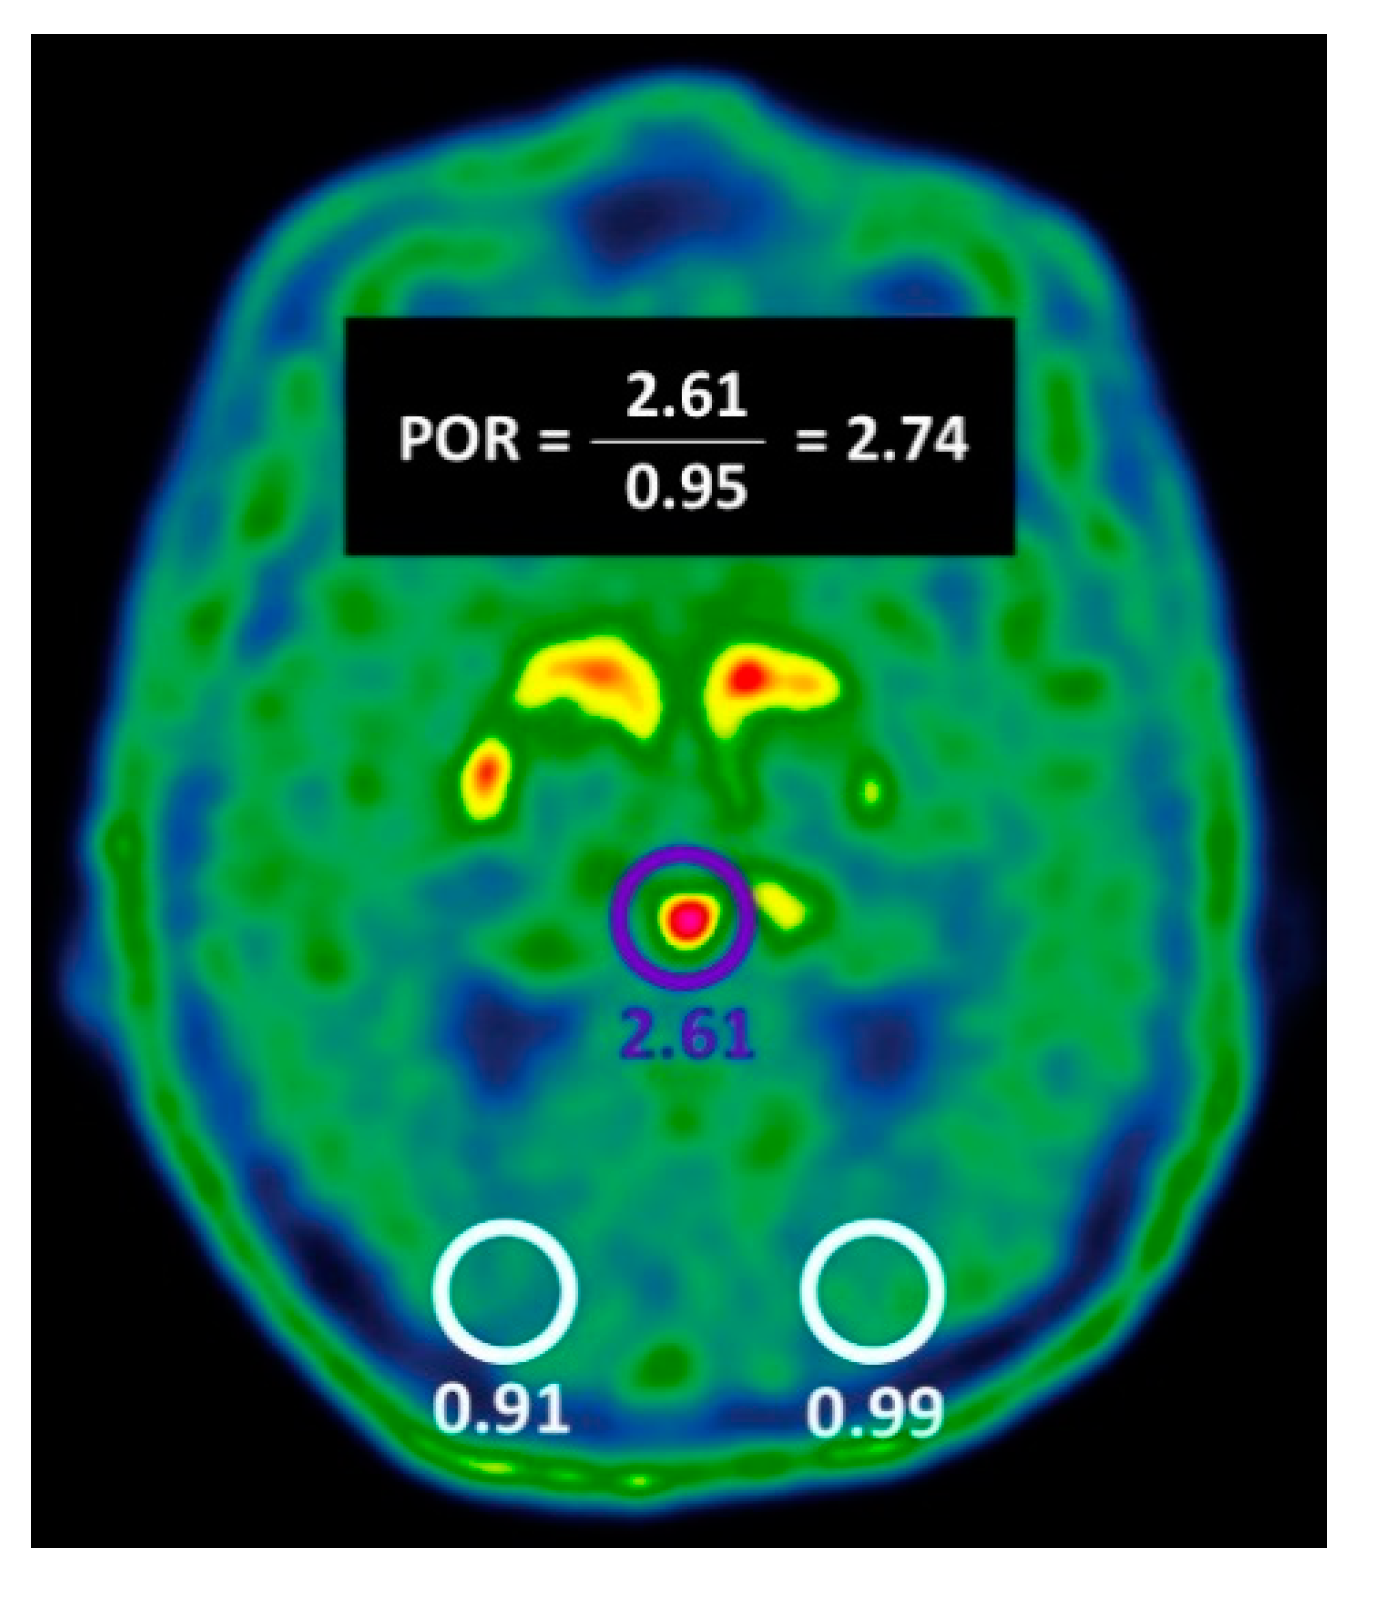

| POR ≥ 1.57 | 44/69 (63.8%) | 11/43 (25.6%) | <0.01 |

| POR ≥ 1.57 | 44/69 (63.7%) | 32/43 (74.4%) | 76/112 (67.8%) | 44/55 (80%) | 32/57 (56.1%) |

| VA-BG OR POR ≥ 1.57 | 68/69 (98.5%) | 29/43 (67.4%) | 97/112 (86.6%) | 68/82 (82.9%) | 29/30 (96.6%) |

| VA-BG AND POR ≥ 1.57 | 37/69 (53.6%) | 43/43 (100%) | 80/112 (71.4%) | 37/37 (100%) | 43/75 (57.3%) |